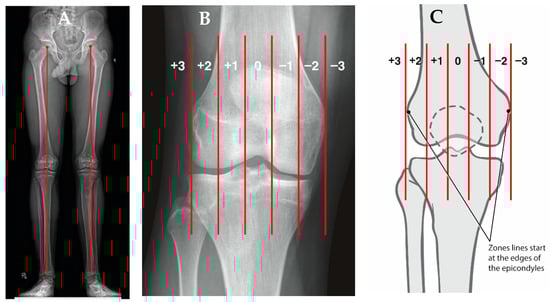

3.1. Coronal Plane Malalignment

- Paley, D.; Tetsworth, K. Mechanical axis deviation of the lower limbs. Preoperative planning of uniapical angular deformities of the tibia or femur. Clin. Orthop. Relat. Res. 1992, 48–64. [Google Scholar]